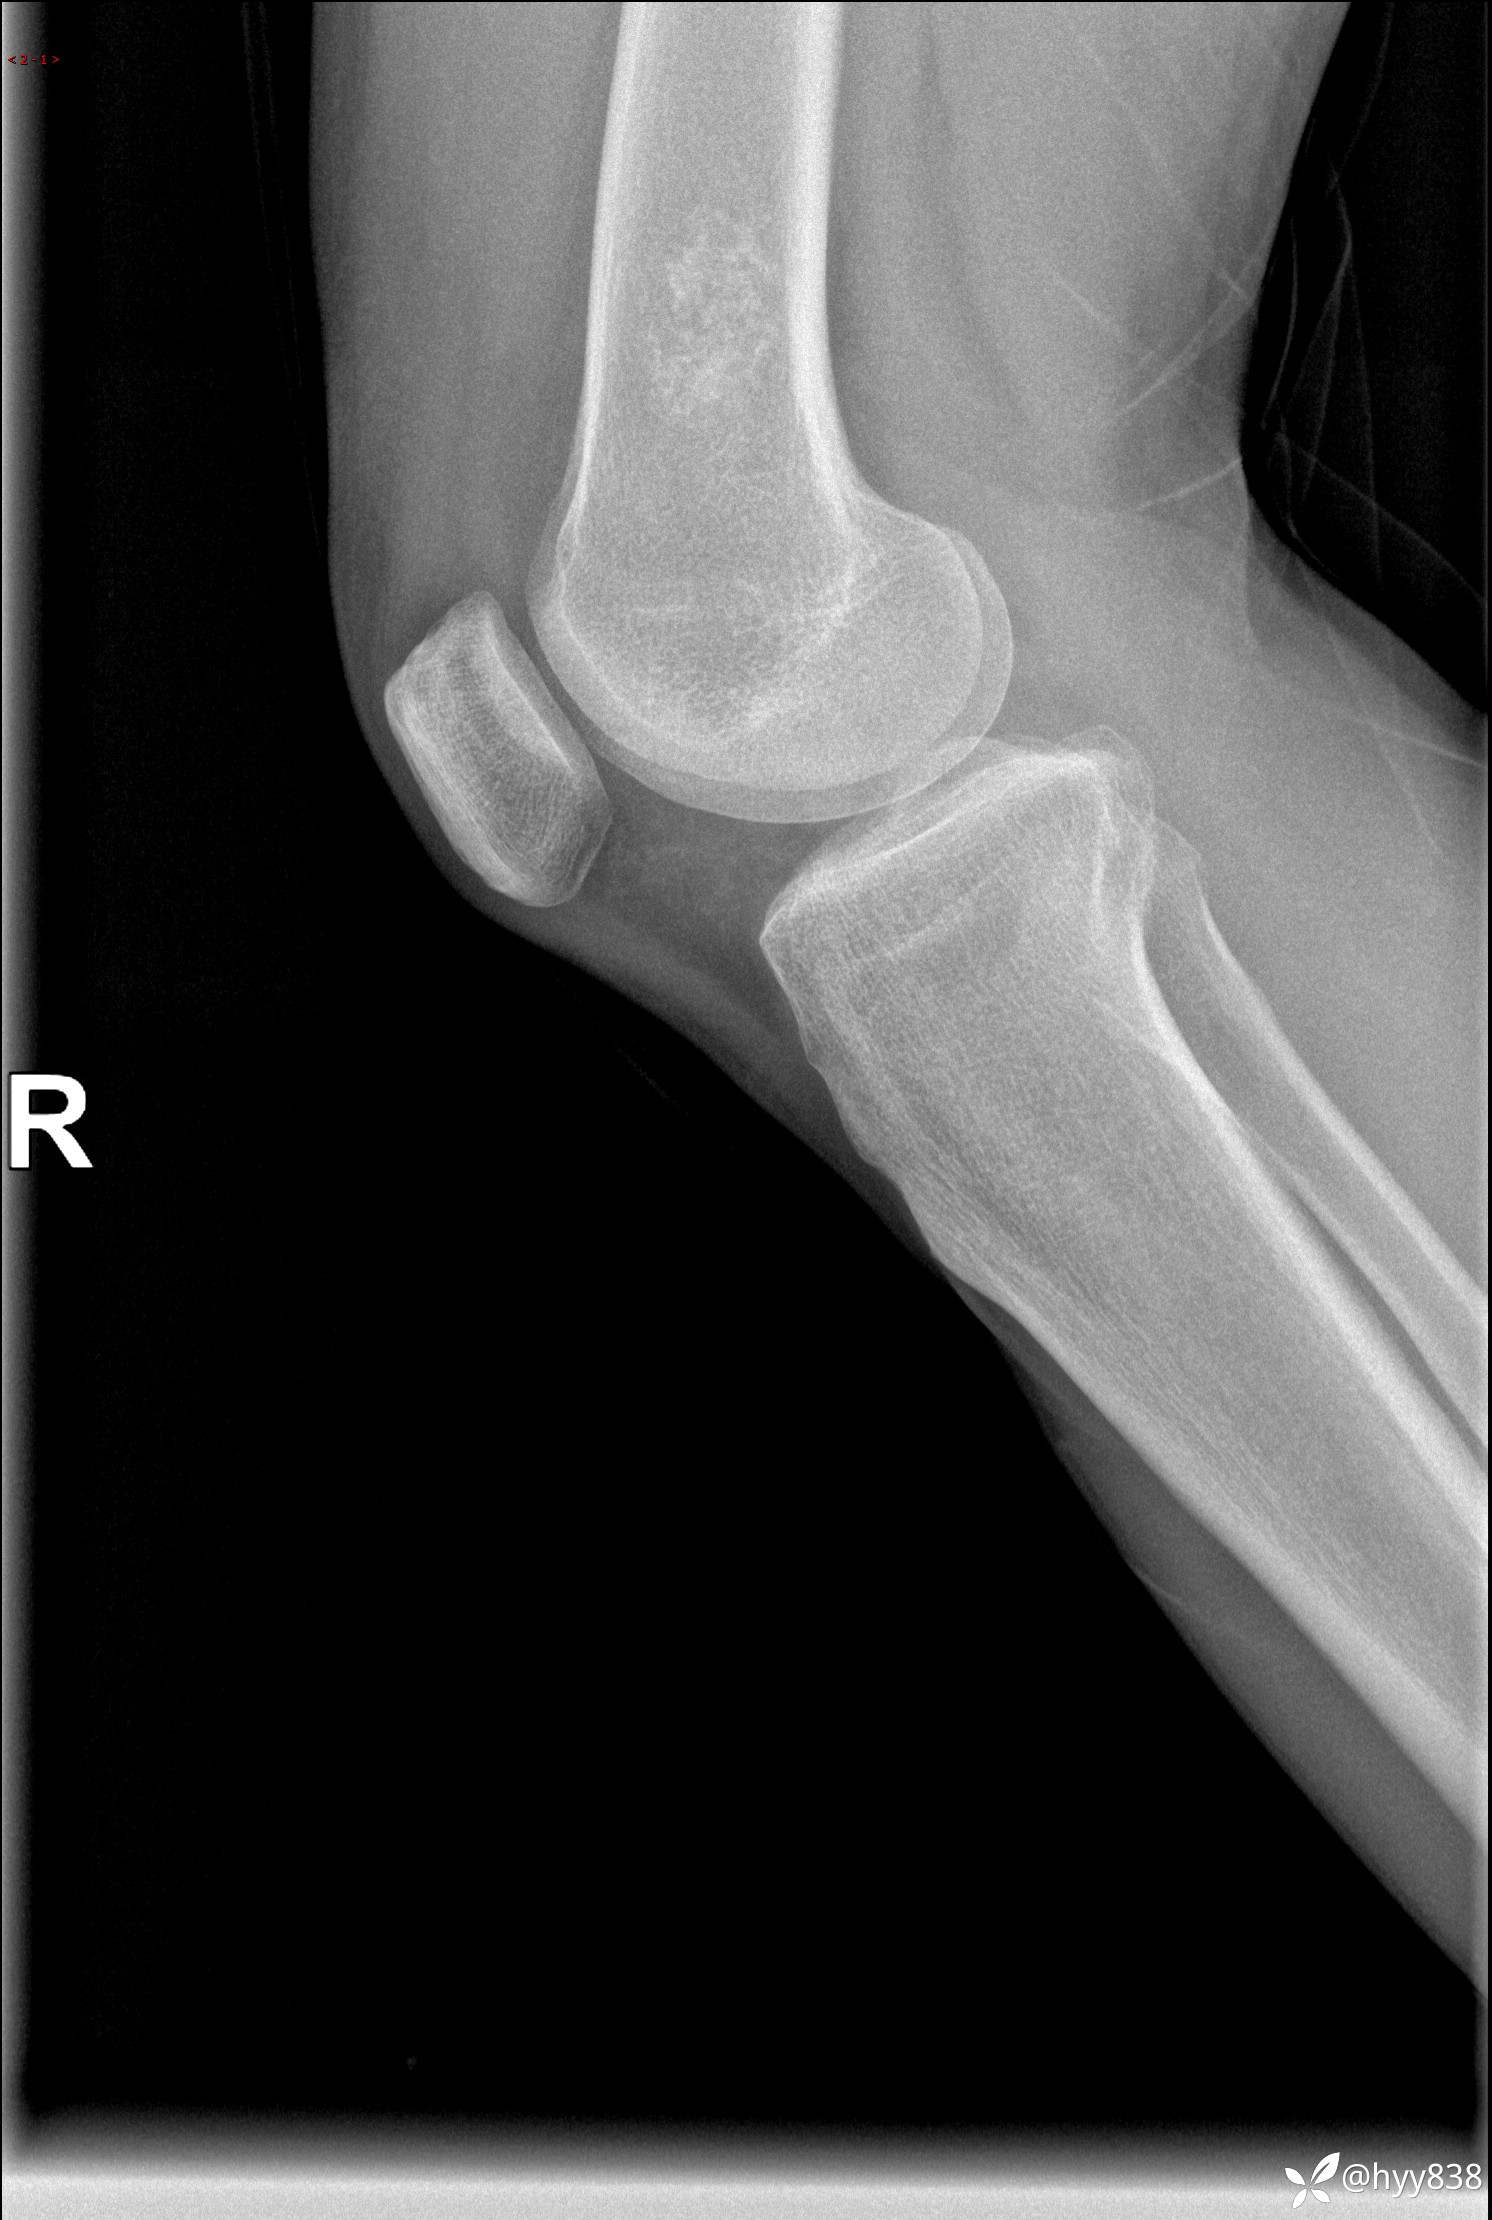

患者性别:男

患者年龄:60岁

主诉:右大腿疼痛不适数月

膝关节平片

内生软骨瘤 (27)